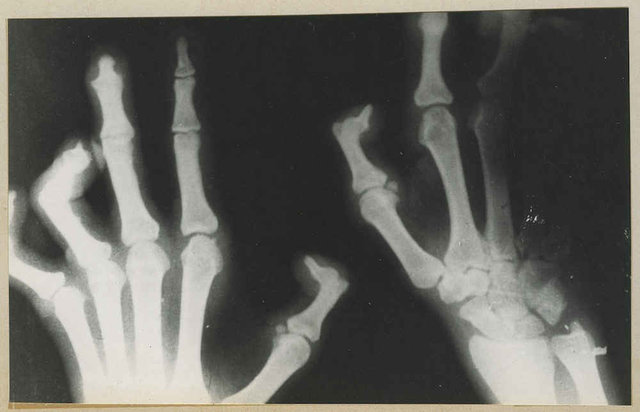

پزشک هماهنگ کننده سل و جذام معاونت امور بهداشتی عامل مولد جذام را یک باسیل از خانواده باسیلهای به وجود آورنده بیماری سل ذکر کرد و گفت: عامل بیماری جذام، تنههای اصلی اعصاب کنترل کننده عملکرد دستها و پاها را درگیر میکند و این نواحی را دچار اختلالات حسی حرکتی میکند و همچنین چشم ها را نیز درگیر و مبتلا میسازد.

به گفته وی، در قدیم شیوه صحیحی برای درمان جذام استفاده نمیشد و بیماری در صورت پیشرفت منجر به معلولیت و تغییر شکل نابهنجار فرد میشد. در برخی مراکز قدیمی نگهداری بیماران شاهد حضور افراد مسنی هستیم که دچار معلولیت ناشی از جذام هستند. این افراد در حال حاضر درمان شدهاند و از بابت سرایت بیماری آنها جای هیچ گونه نگرانی نیست.